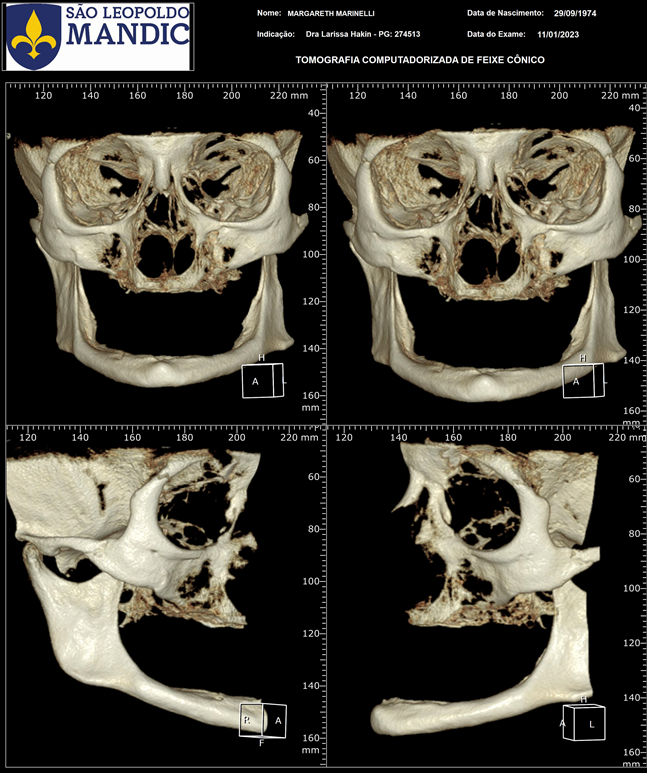

Foi feito então a avaliação clínica e de exames complementares de imagem (Figura 2).